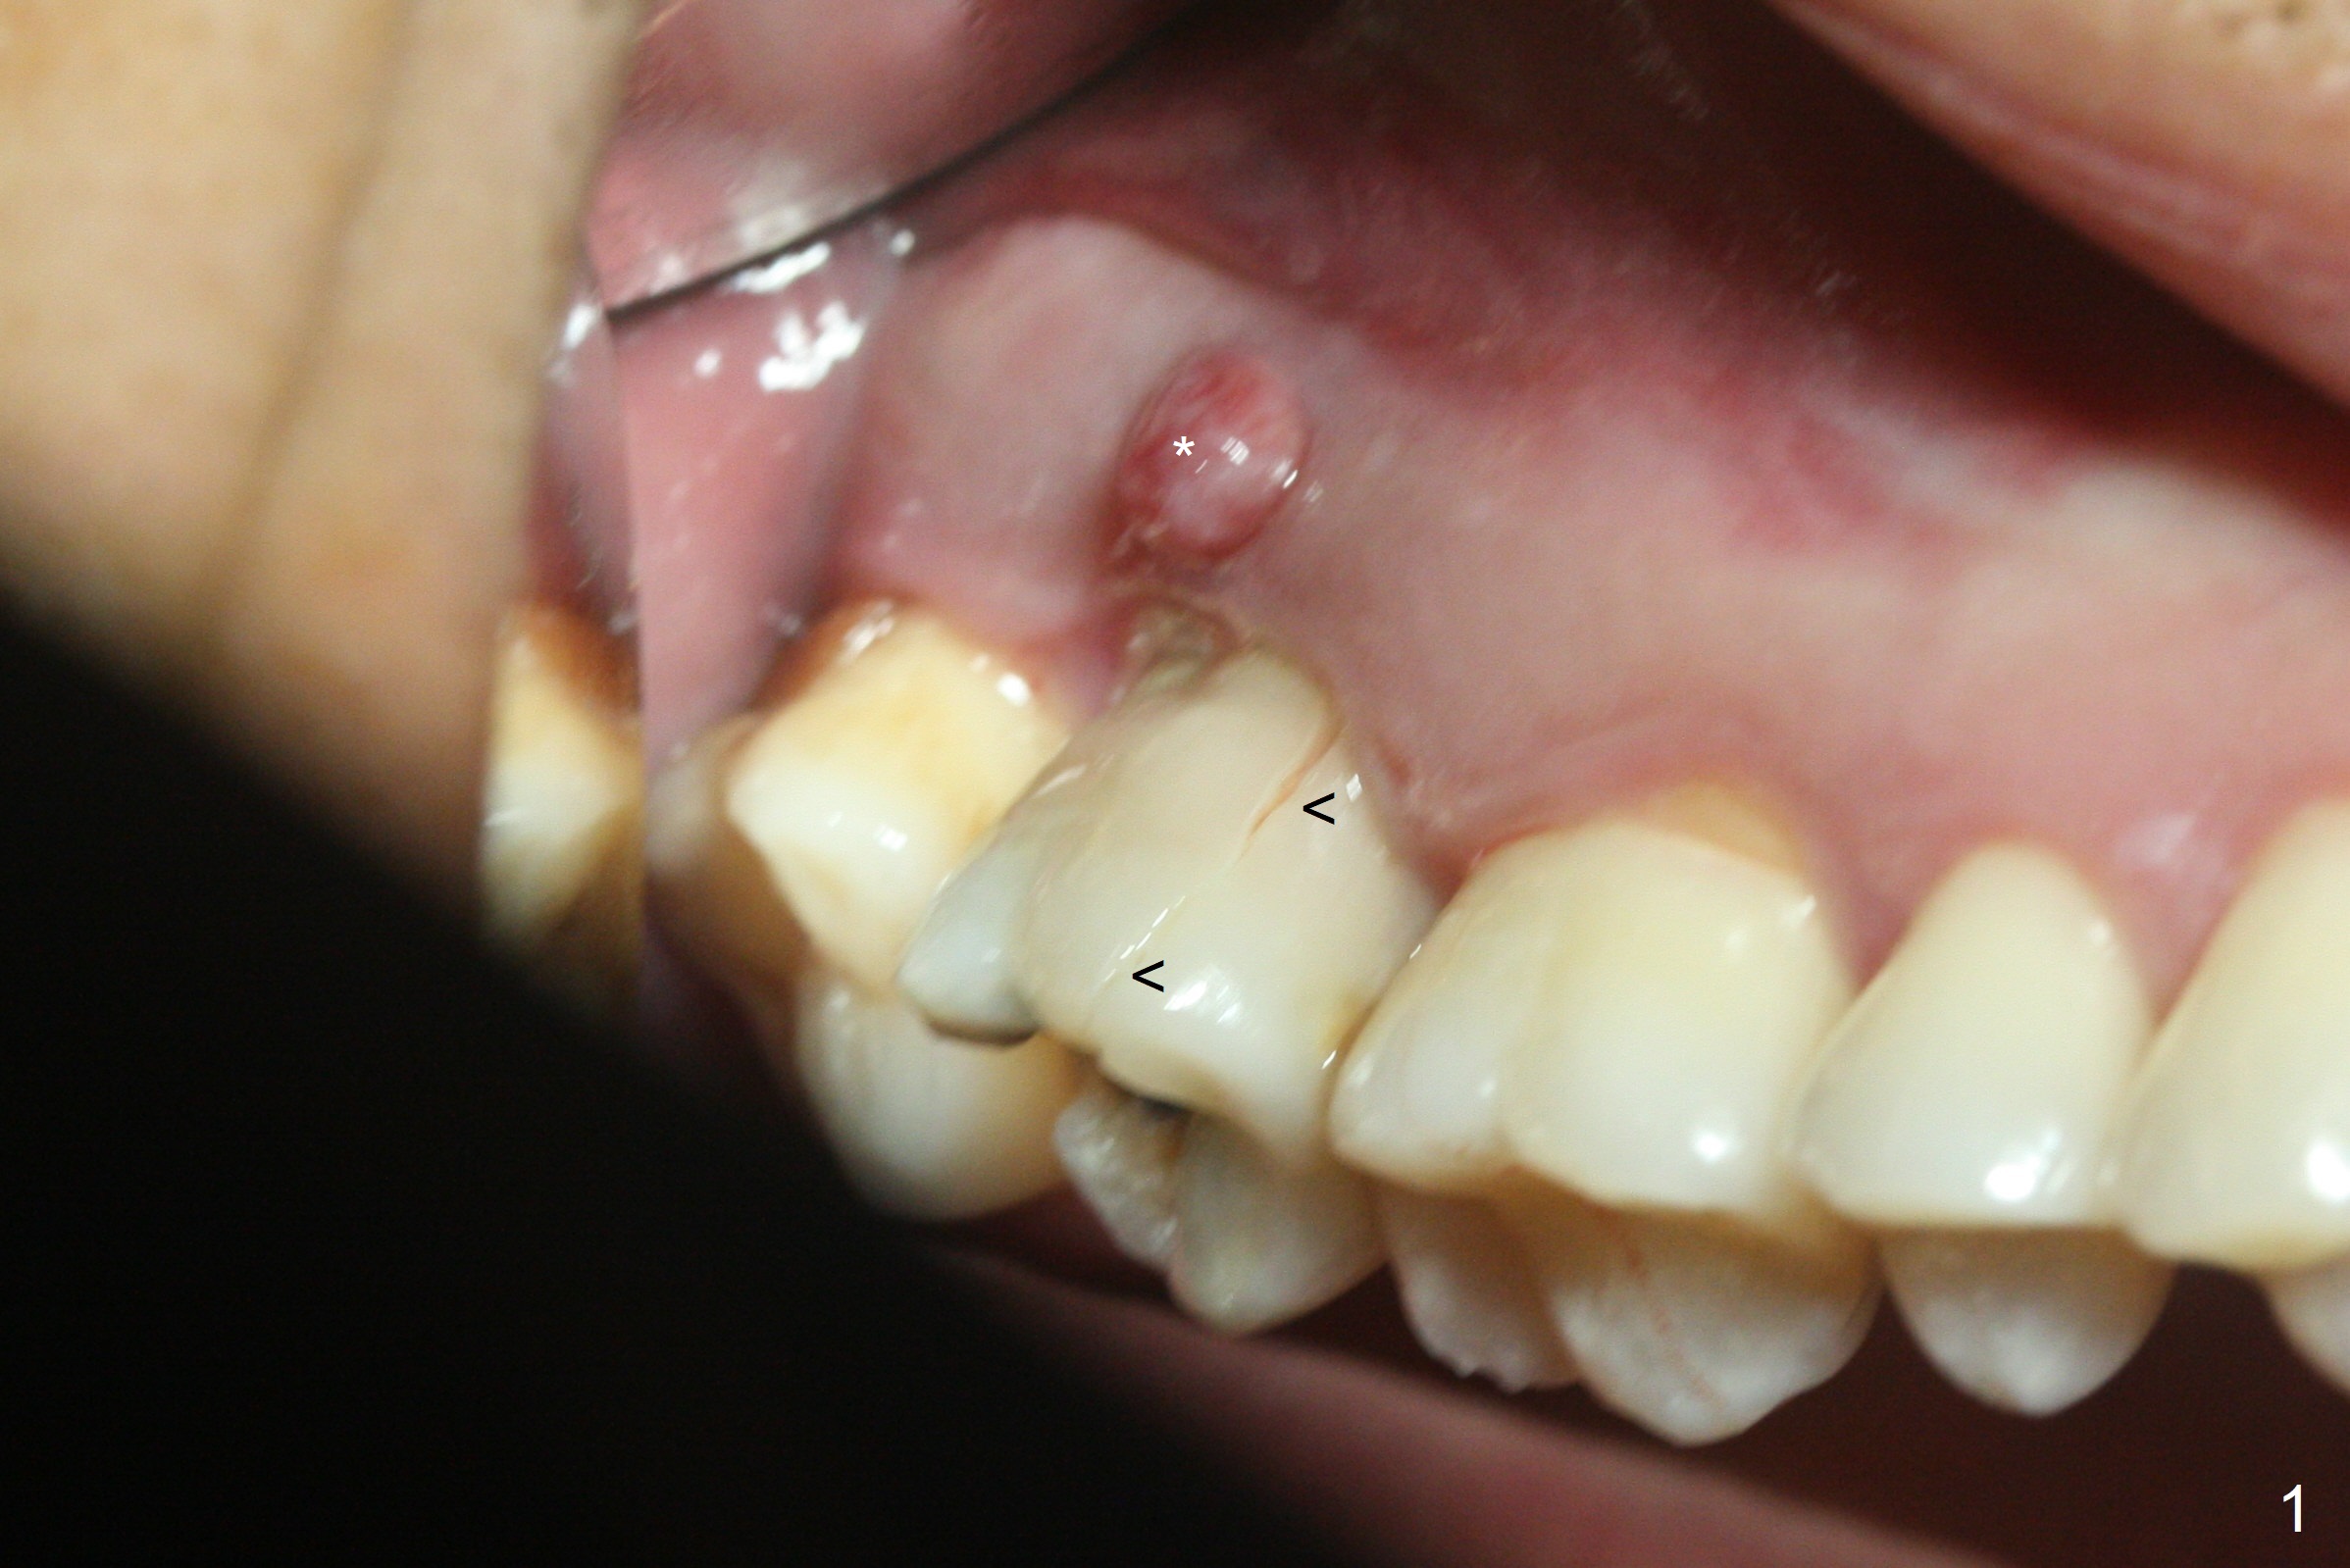

When the 59-year-old man returns for #24 implant placement, the tooth #2 is found to have crack (Fig.1,2 arrowheads), associated with buccal and palatal fistulae (*) and loss of amalgam (Fig.4 *). Abundant granulation tissue is attached to the roots of the affected tooth (Fig.3), indicating severe bone loss. There is a plateau associated with the septum and buccal sockets, which is the site of osteotomy. Magic split and 3 and 3.8 mm Magic Expanders are used to initiate osteotomy. After use of 4.3 mm Magic Drill for about 3 mm, Osteogen plug and allograft are used for sinus lift, followed by insertion of a 4.5x11 mm dummy implant (Fig.5). When a 5.5x9 mm dummy implant is placed with stability, it appears to be seated cervical (Fig.6,7). When a 6x9 mm IBS implant (definitive) is placed with a 6.5x5.5(4) mm abutment, they are seated too deep for provisional (Fig.8). The implant/abutment are removed and replaced by a 6.5x11 mm one in a shallower position; after trimming the same abutment as mentioned above (Fig.9), an immediate provisional is fabricated to keep bone graft in place. Fabrication of Tap with soft tissue markers will reduce the chance of miscalculation and waste of implants. The coronal threads of the implant are covered with bone 6 months postop (Fig.10). One month later when a permanent crown tries in, the implant is found to be loose and tender. A healing abutment is placed. Six months later, the patient returns for crown retry-in. The tooth #1 seems to have shifted mesially (Fig.11 arrow). When the abutment is placed, the implant remains tender and loose. After implant removal with a wrench, there is no granulation tissue or bony defect, including the intact sinus floor (Fig.12 <). Since the tooth #1 has deep periodontal pockets and mobility, the tooth is extracted with abundant granulation tissue. After debridement, Osteogen plug is placed in the socket of #1, while Vanilla graft is placed at the site of #2 (Fig.13 *). Three weeks later, the socket of #2 heals with exposure of Osteogen plug (Fig.14 (B: buccal)).